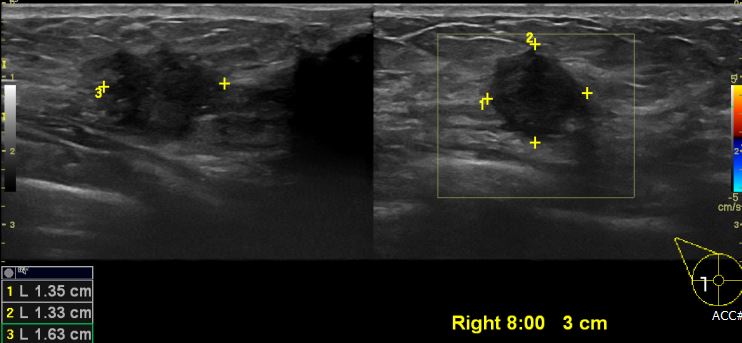

상기환자 우측 만져지는 멍울로 내원하신 30대 여성분으로 우측 8시방향에서 3cm

떨어진 거리의 혹 조직검사 시행하여 우측 침윤성 유관암 진단 되었습니다.